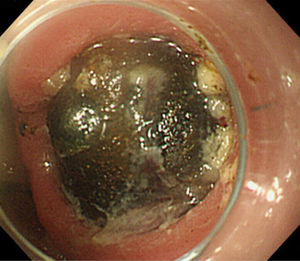

Figure 1.

A coronal CT scan shows the impacted stone (arrow) in the first portion of the duodenum and the marked gastric distension.